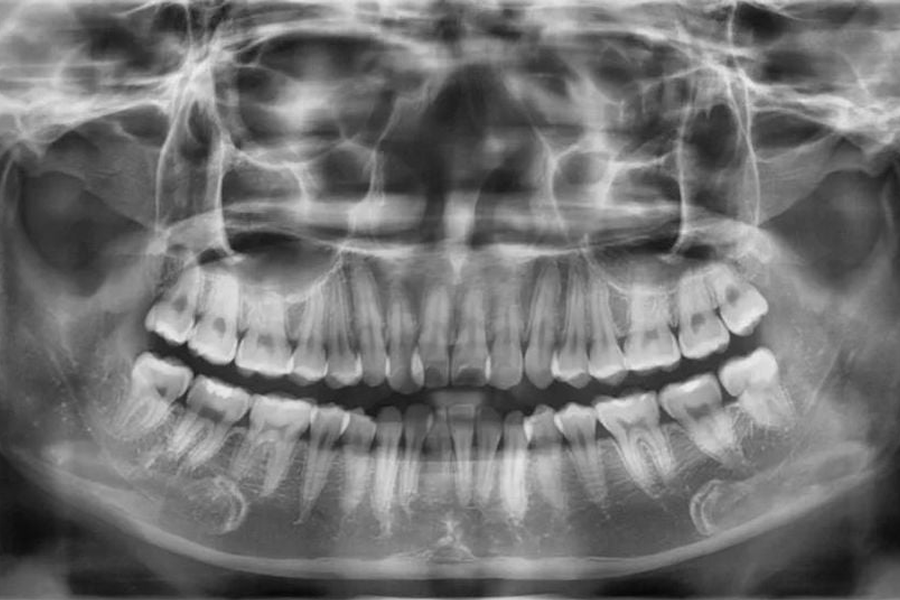

Để thực hiện niềng răng các bác sĩ phải lên phác đồ điều trị cụ thể đối với từng trường hợp. Để có thể chẩn đoán chính xác và lên kế hoạch điều trị hợp lý, bác sĩ phải hiểu rõ đặc điểm xương hàm, trục răng, mức độ lệch lạc của răng và độ cứng chắc của răng như thế nào... Do vậy chụp Xquang trước kh niềng rang là việc rất cần thiết. Thông qua những hình ảnh thu được từ việc chụp phim Xquang khi niềng răng kết hợp với hình ảnh thăm khám khoang miệng, ngoài mặt, lấy dấu mẫu hàm, bác sĩ mới có thể đưa ra được những nhận định và phán đoán chính xác về tình trạng răng, hướng dịch chuyển của răng sau khi niềng và lên phác đồ cụ thể cho từng trường hợp.

Niềng răng trong chỉnh nha là một điều trị trong khoảng thời gian dài, từ 2 - 3 năm, điều này có thể khiến bác sĩ không thể nhớ hết được những điều trị của mình cũng có thể bệnh nhân sẽ quên đi hàm răng trước khi niềng của bản thân. Vì vậy việc chụp Xquang sẽ cho phép bác sĩ và bệnh nhân có cái nhìn toàn diện và chính xác hơn trong quá trình niềng răng.

Bên cạnh đó, chụp phim Xquang là một trong những cách lưu trữ thông tin về tình trạng răng và xương hàm của bệnh nhân, dựa vào các hình ảnh trên phim qua các lần chụp bác sĩ và bệnh nhân có thể thấy được sự di chuyển của răng cũng như hiệu quả quá trình điều trị chỉnh nha.